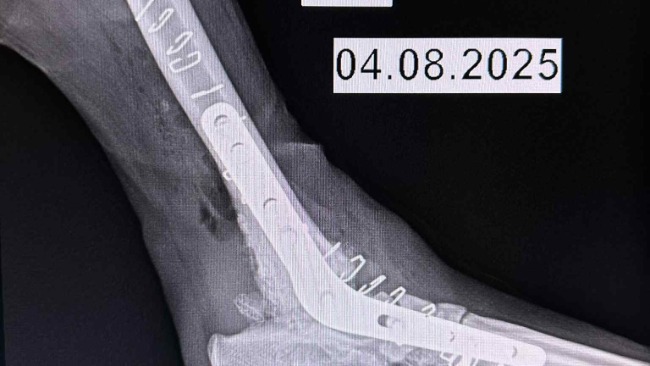

Niedawno Zenek przeszedl ciezka operacje artrodezy ,ratujaca jego łapke .Koszt operacji wyniosl 10tys,dzieki temu ma szanse ocalic lapke i zyc bez bolu .

Niestety Zenek nadal potrzebuje wsparcia ,puscila jedna ze srub ,znowu operacja i dalsze koszty .Prosze pomozcie